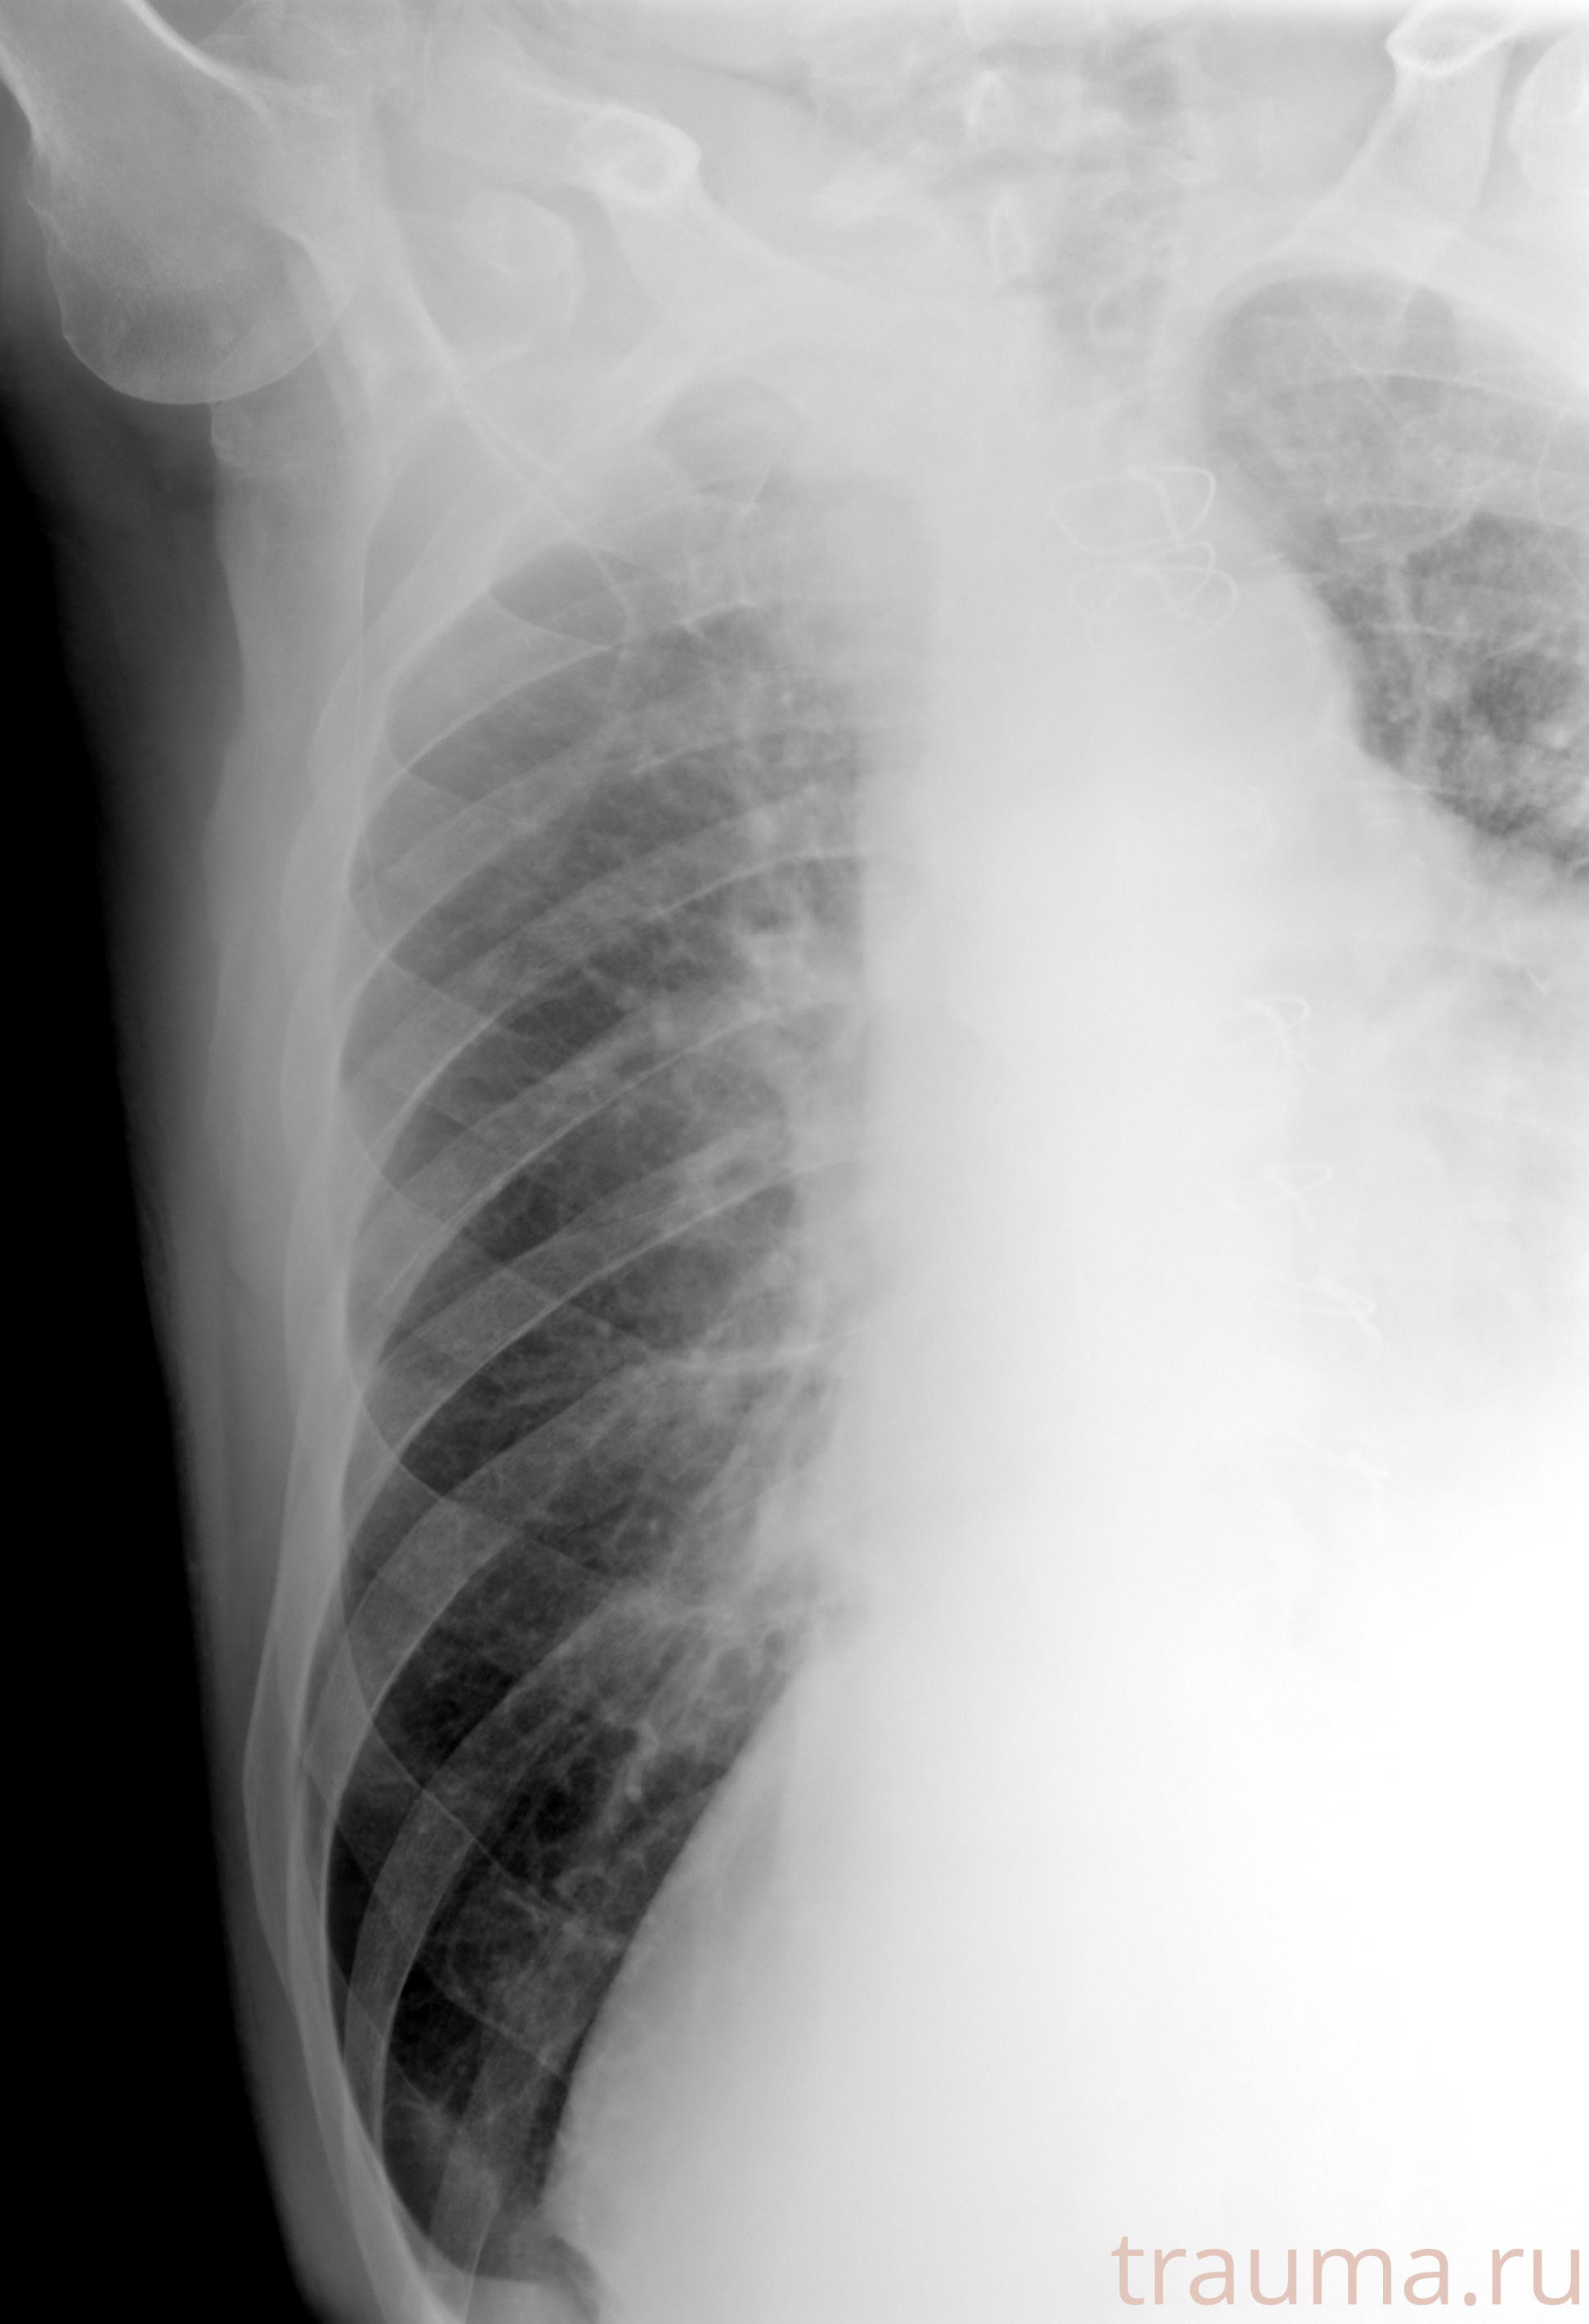

Рентген на дому: по вашему адресу приезжает врач-рентгенолог, травматолог-ортопед с мобильным рентгеновским аппаратом, проводит диагностику травмы или заболевания, делает необходимые рентгенограммы, дает рекомендации по дальнейшему лечению. Получить качественные снимки в домашних условиях возможно благодаря уникальной методике, разработанной МосРентген Центром для института  Склифосовского

при переломе шейки бедра и пневмонии от компании МосРентген Центр - партнера Института имени Склифосовского